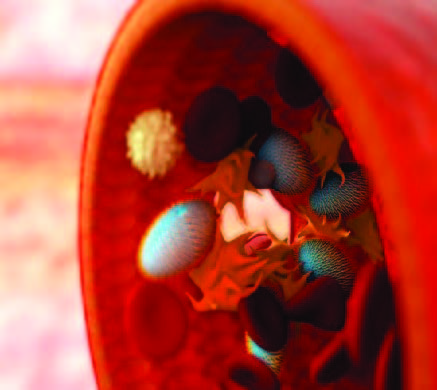

LOS ANGELES (TIP): Scientists, including two of Indian-origin, have developed new synthetic platelets that mimic and outperform natural platelets at controlling bleeding. Researchers at the University of California, Santa Barbara turned to the human body’s own mechanisms for inspiration in dealing with the necessary and complicated process of coagulation. By creating nanoparticles that mimic the shape, flexibility and surface biology of the body’s own platelets, they were able to accelerate healing processes while opening the door to therapies and treatments that can be customised to specific patient needs.

“This is a significant milestone in the development of synthetic platelets, as well as in targeted drug delivery,” said Samir Mitragotri, director UC Santa Barbara’s Centre for Bioengineering. The plateletlike nanoparticles (PLNs) behave just like their human counterparts and can be added to the blood flow to supply or augment the patient’s own natural platelet supply, stemming the flow of blood and initiating the healing process, while allowing physicians and other caregivers to begin or continue the necessary treatment. Emergency situations can be brought under control faster, injuries can heal more quickly and patients can recover with fewer complications, researchers said.

“We were actually able to render a 65 per cent decrease in bleeding time compared to no treatment,” said graduate student researcher Aaron Anselmo, lead author of the paper. According to Mitragotri and colleagues Stefano Menegatti and Sunny Kumar, the key lies in the PLNs’ mimicry of the real thing. By imitating the shape and flexibility of natural platelets, PLNs can also flow to the injury site and congregate there. With surfaces functionalised with the same biochemical motifs found in their human counterparts, these PLNs also can summon other platelets to the site and bind to them, increasing the chances of forming that essential plug.

The platelets are engineered to dissolve into the blood after their usefulness has run out, minimising complications that can arise from emergency hemostatic procedures. According to Anselmo’s investigations, for the same surface properties and shape, nanoscale particles can perform even better than micron-size platelets. This technology allows for customisation of the particles with other therapeutic substances – medications, therapies and such – that patients with specific conditions might need. “This technology could address a plethora of clinical challenges,” said Dr Scott Hammond, director of UCSB’s Translational Medicine Research Laboratories. With optimisable PLNs, physicians would be able to strike a fine balance between anticoagulant therapy and wound healing in older patients, by using nanoparticles that can target where clots are forming without triggering unwanted bleeding.